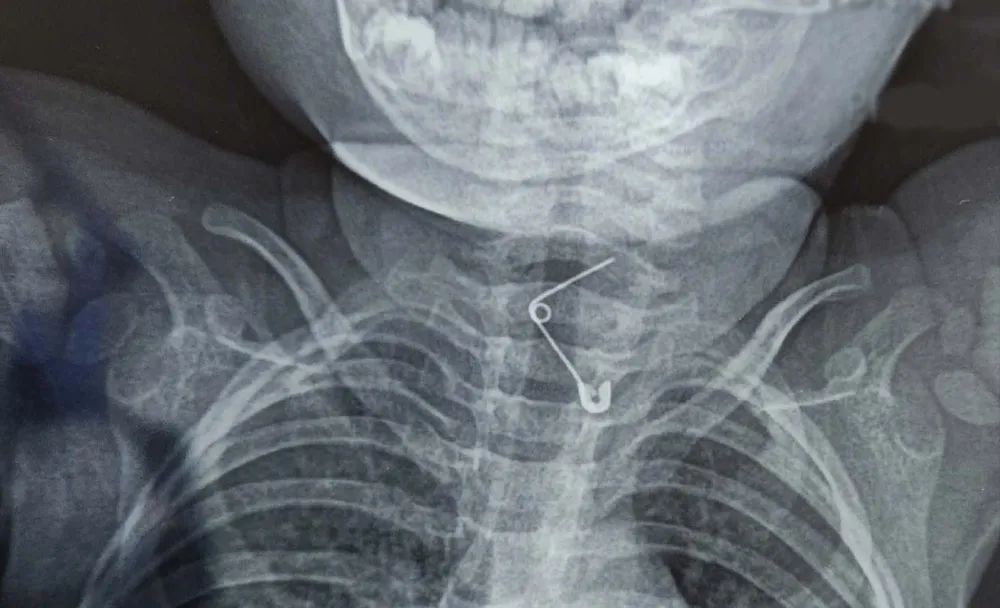

Tại Khoa Cấp cứu, qua thăm khám và hình ảnh nội soi, bác sĩ phát hiện cây kim băng dài khoảng 3cm đã bung ra thành hình chữ L. Đầu nhọn kim ghim vào thành thực quản gây nguy cơ thủng, chảy máu và nhiễm trùng rất cao.

Hình ảnh phim XQ phát hiện kim băng trong thực quản bệnh nhi